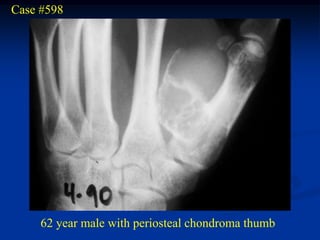

Case #598

62 year male with periosteal chondroma thumb

Axial T-1 MRI

Coronal proton density MRI

T-2 MRI

Photomic